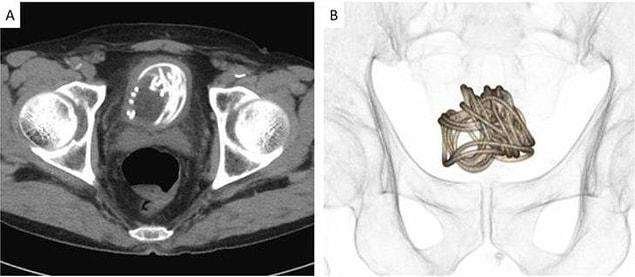

Ağrısı olduğu için Dokkyo Üniversitesi Tıp Fakültesi’ne giden 79 yaşındaki adamın penisinden 2 metrelik atlama ipi çıktı.

Uzmanlar, idrar yapma konusunda zorluk yaşadıktan sonra röntgeni çekilen adamla ilgili daha önce böyle bir görmediklerini dile getirdi.

Profesör Toshiki Kijima, ipin uzunluğu ve mesaneye dolanması düşünüldüğünde transüretral ekstraksiyon zor olduğunu belirtti.

Mesaneye yerleşen ip, mesane kasıldıkça kıvrıldığı için ameliyatla karnından çıkarıldı.